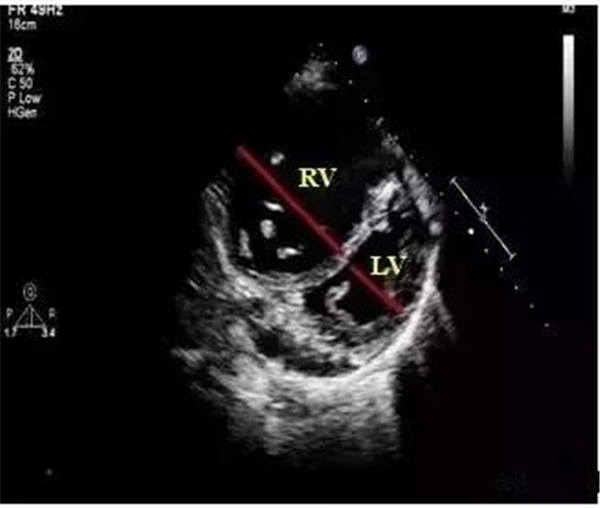

室間隔運動異常

主要表現為左室短軸切面“D”型改變。此時,室間隔偏向左室側,運動平直,收縮期運動幅度減低,與右室前壁及左室后壁運動不同步。